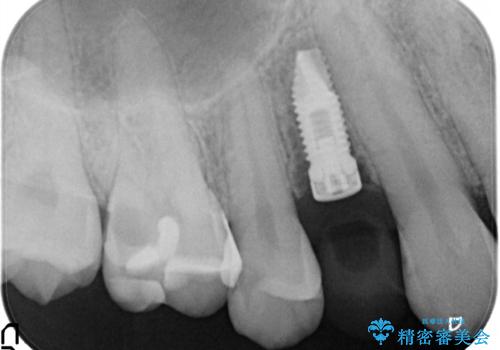

- 歯根破折により抜歯となってしまった患者様です。

インプラントによる咬合回復を行いました。